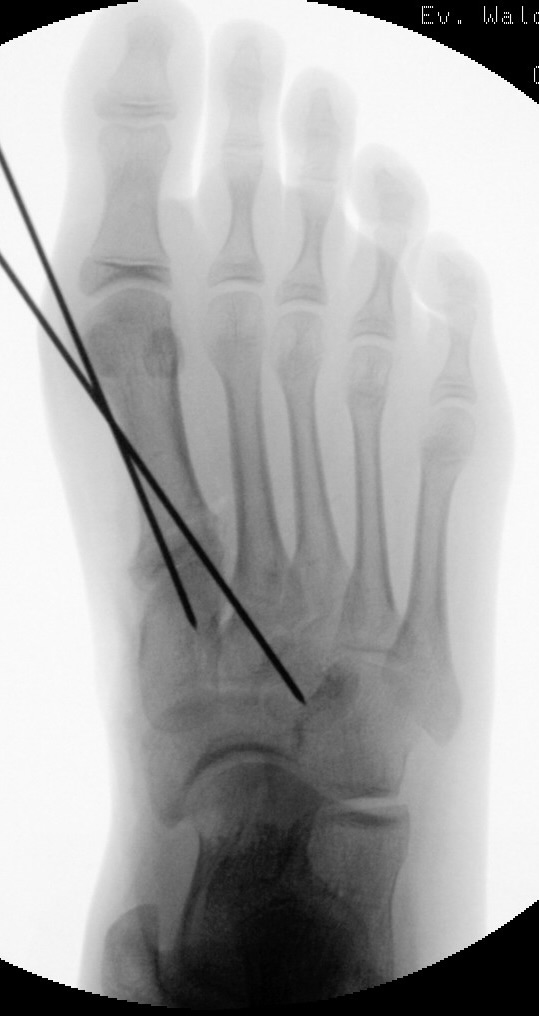

In der Regel bestehen aktive Wachstumsfugen bei Mädchen bis zum 12. und bei Jungen bis zum 14. Lebensjahr, mit Abweichungen von einem Jahr nach unten und nach oben. Präzise Informationen unter anderem darüber gibt das präoperative Röntgenbild (Abb. 2).

Abb. 2 a-c: offene Wachstumsfugen MT I Basis und Zehen (a), teilweise geöffnete Wachstumsfugen (b) und geschlossene Wachstumsfugen (c).

Zum Lesen der Bildbeschreibung und zur Vollansicht bitte die Bilder anklicken. Bilder: A. Helmers.